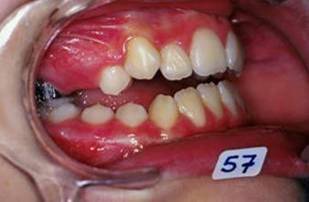

En fouillant dans mes cas j'ai trouve celui ci qui presente une beance assez importante. Je me suis rappele qu'un certain message etait lance il y a qq temps a propos d'un enfant qui presente une beance et de savoire comment faire dans ce cas. Je pense qu'il est interessant de voir comment les uns et les autres prennent en charge ce type de cas. Il s'agit d'un fille de 12 ans, succion de pouce, interposition linguale totale, beance de molaire a molaire, respiration mixte, incompetence labiale au repos, fonction labiale serree. Le total quoi!!! Voici la premiere serie de photos